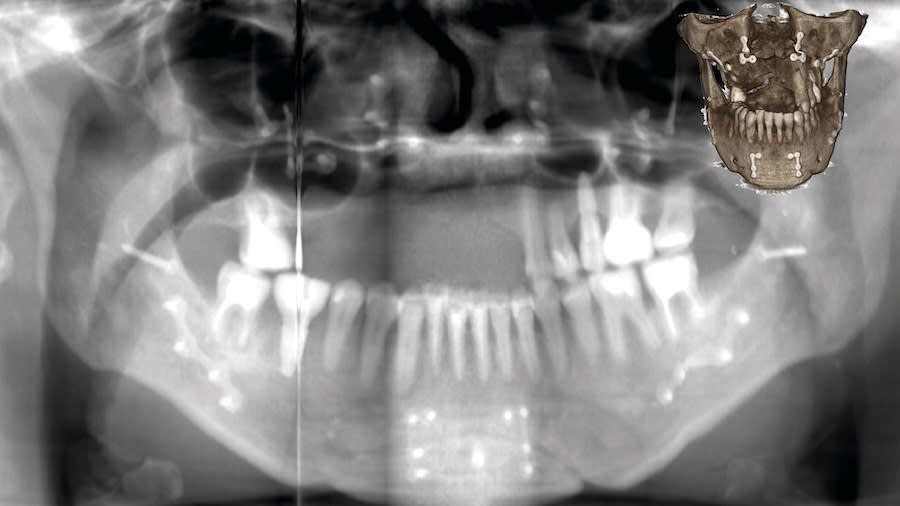

Case 1 (Figure 3 through Figure 24) depicts a 3-year follow-up of combined osseodensification sinus protocol IV in a severely resorbed maxillary ridge with ≤0.5 mm bone height in molar sites and horizontal deficiency at the first premolar site, using a two-stage approach for implant placement.

Case 2 (Figure 25 through Figure 36) illustrates a 3-year follow-up of the osseodensification sinus protocol IV in a severely resorbed right maxillary ridge with <0.5 mm bone height in molar sites, using a two-stage approach for implant placement.

Case 3 (Figure 37 through 44) shows a case of significant trauma history with a 3-year follow-up of the osseodensification sinus protocol IV in a severely resorbed right maxillary ridge with ≤0.5 mm bone height in molar sites, using a two-stage approach for implant placement.